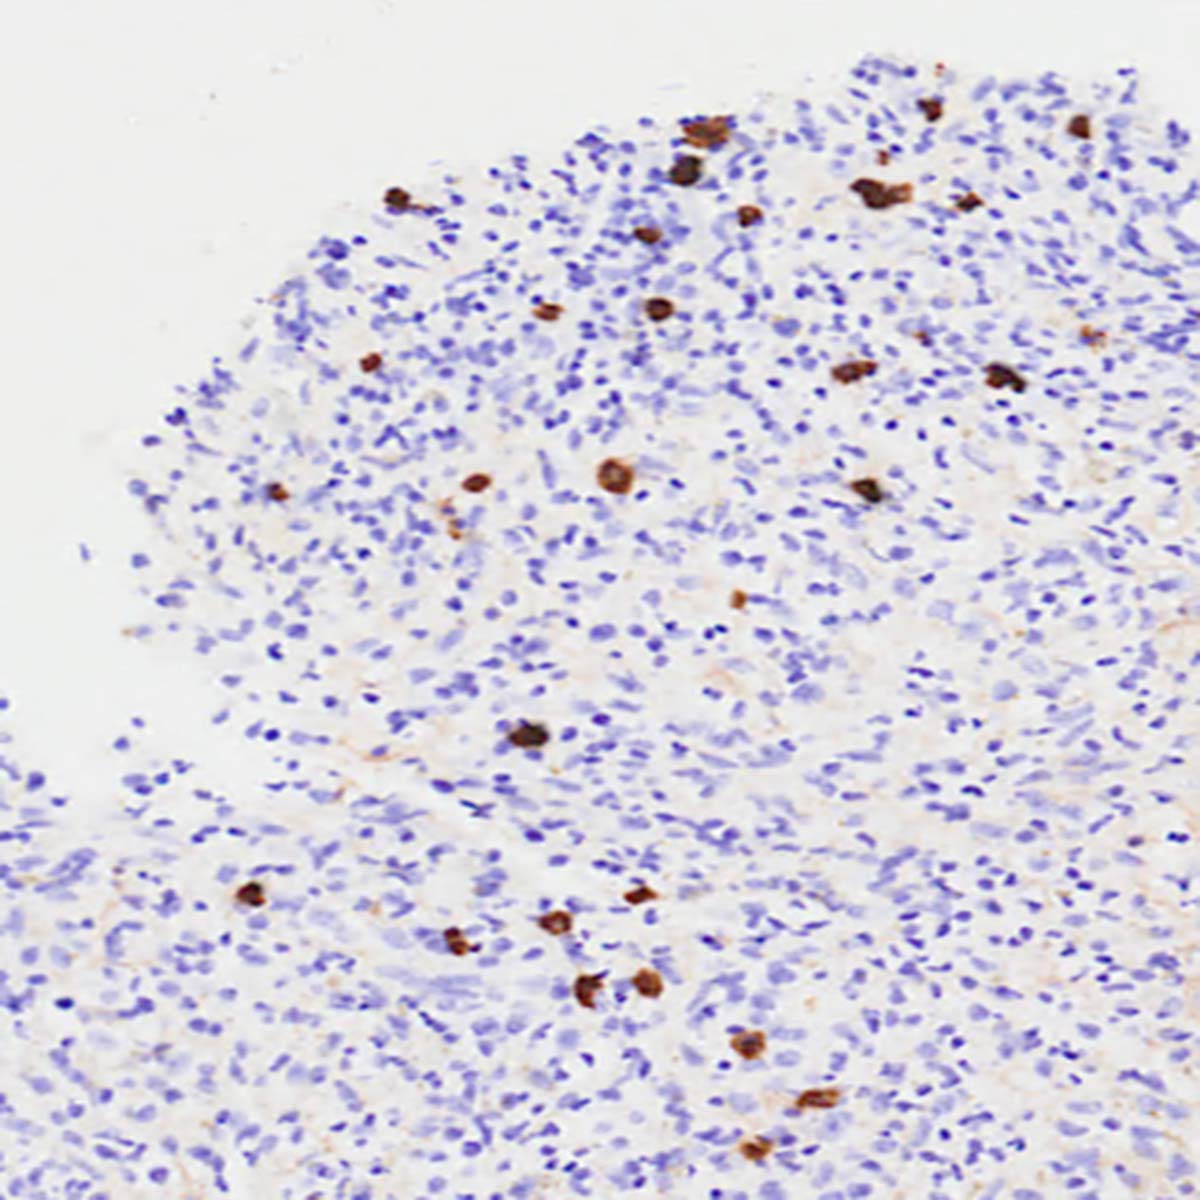

IgG4関連疾患の主な組織病理学的特徴 (文献 1)より)

| 組織学的所見 | 特徴 | 組織学的顕微鏡写真 |

|---|---|---|

| IgG4陽性形質細胞の増加 | IgG4+ 形質細胞の上昇 (ほとんどの臓器で >10 細胞/HPF、膵臓と腎臓 >50 細胞/HPF) は診断をサポートしますが、単独では十分ではありません。この場合、IgG4陽性形質細胞はIgG陽性形質細胞集団全体の>40%を占めており、これはIgG4関連疾患の2019 ACR/EULAR分類における主要な診断基準となります。 (IgG4免疫染色、×400) | ![]() |